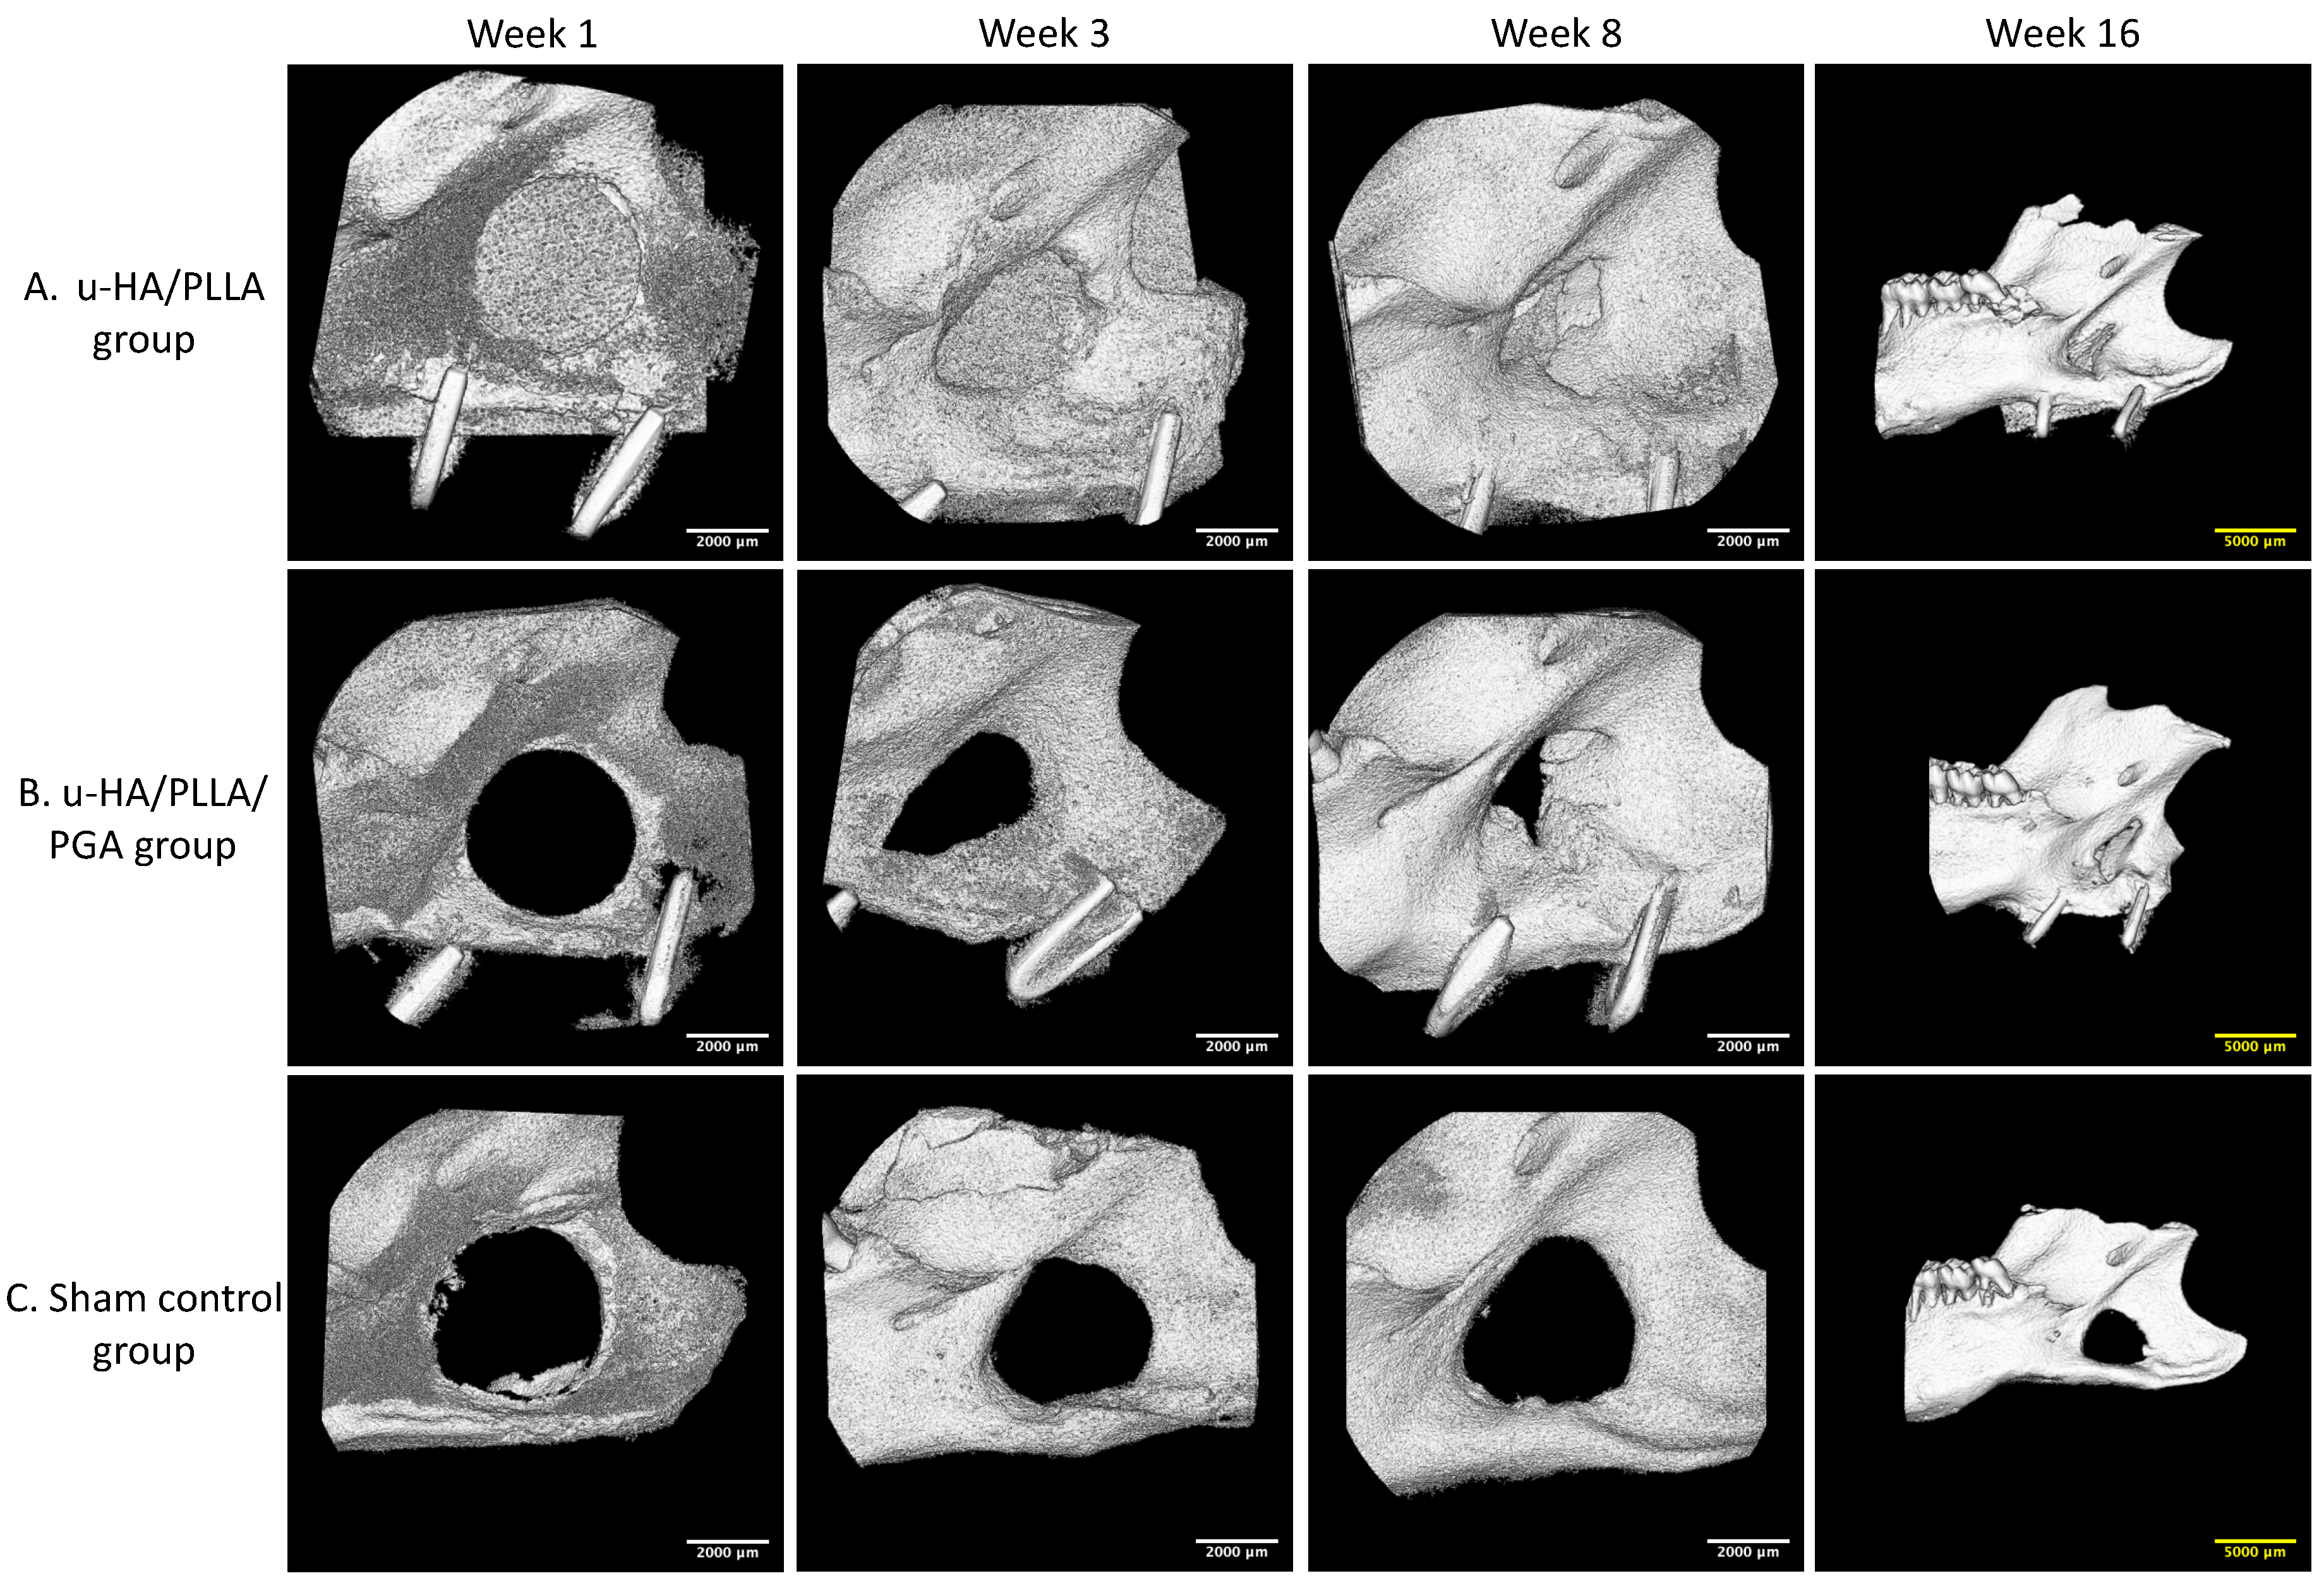

3.1. Micro-CT Evaluation